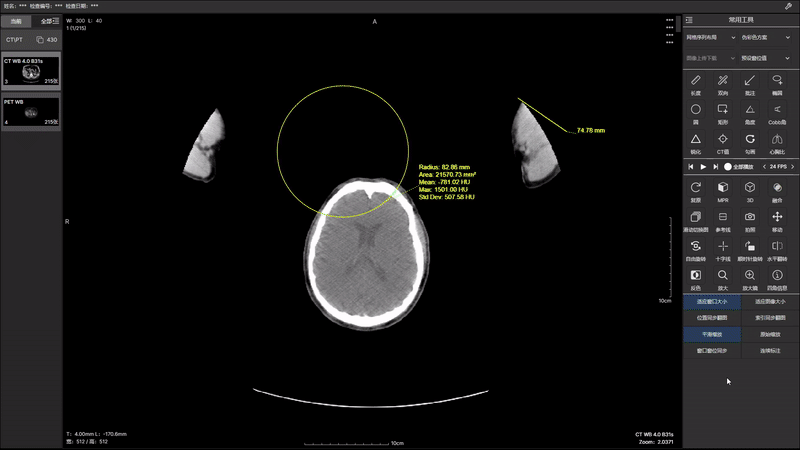

通过先进的算法和技术,我们在 2.0 版本中实现了 PT(正电子发射断层扫描)和 CT(计算机断层扫描)图像的无缝融合。这项突破性技术将为医生提供更全面、 更立体的患者图像,并且2.0 版本的图像融合带来了更高的分辨率和更丰富的图像细节。医生能够更准确地识别病变、评估组织状态,提高诊断的灵敏性和特异性, 为患者制定个性化的治疗方案提供更强有力的支持。医生可以更轻松地导航和比对 PT 和 CT 图像,提高工作效率。智能化的界面设计使操作更直观。 升级你的医学影像诊断体验,与 PT CT 图像融合 2.0 版本一同开启医学影像新时代。提升准确性,优化工作流程,为患者提供更全面的医疗服务。